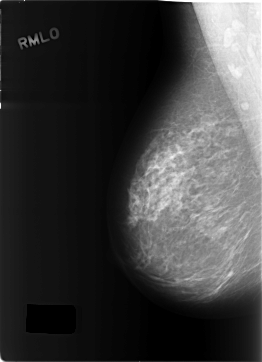

C_0288_1.RIGHT_MLO

RIGHT_MLO LINES 5784 PIXELS_PER_LINE 4192 BITS_PER_PIXEL 12 RESOLUTION 50 NON_OVERLAY